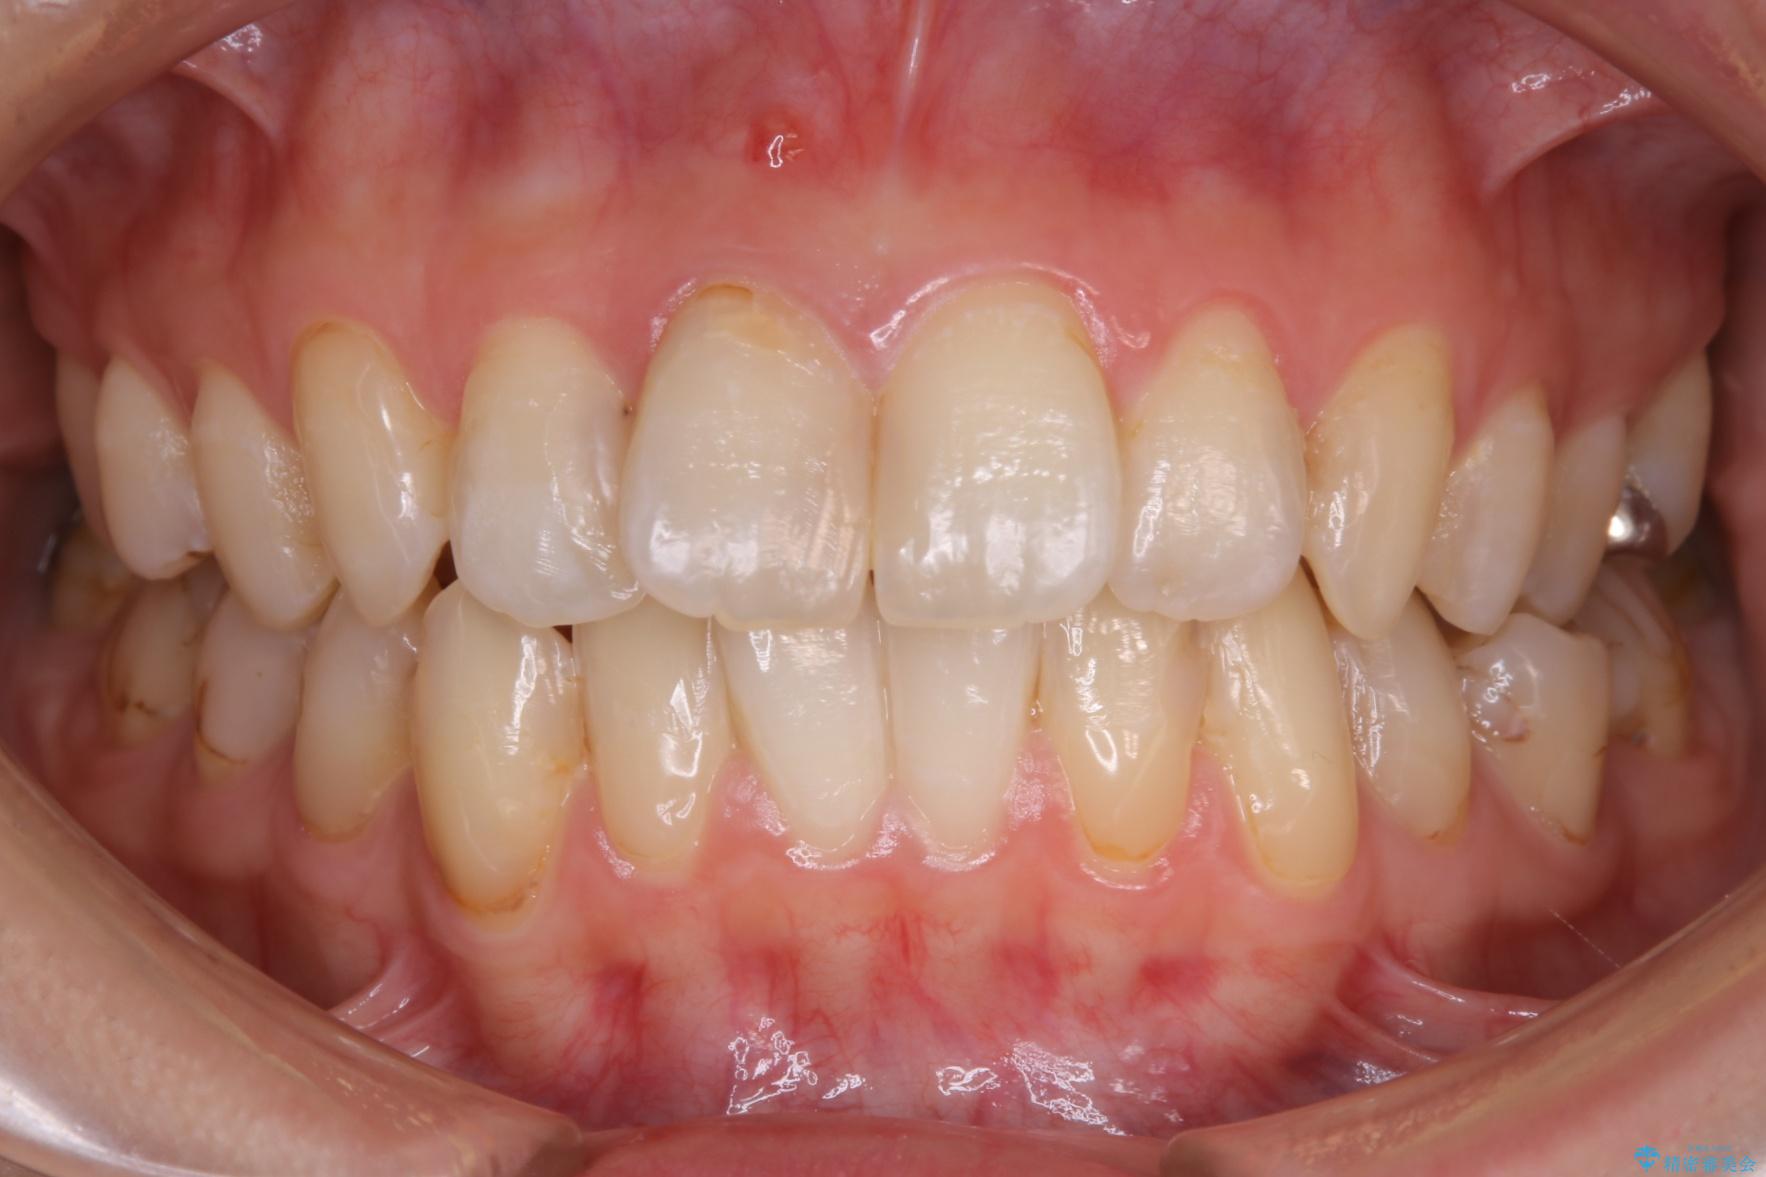

治療後

20代 女性 非抜歯で歯列をコンパクトに20代 女性 非抜歯で歯列をコンパクトに20代 女性 非抜歯で歯列をコンパクトに